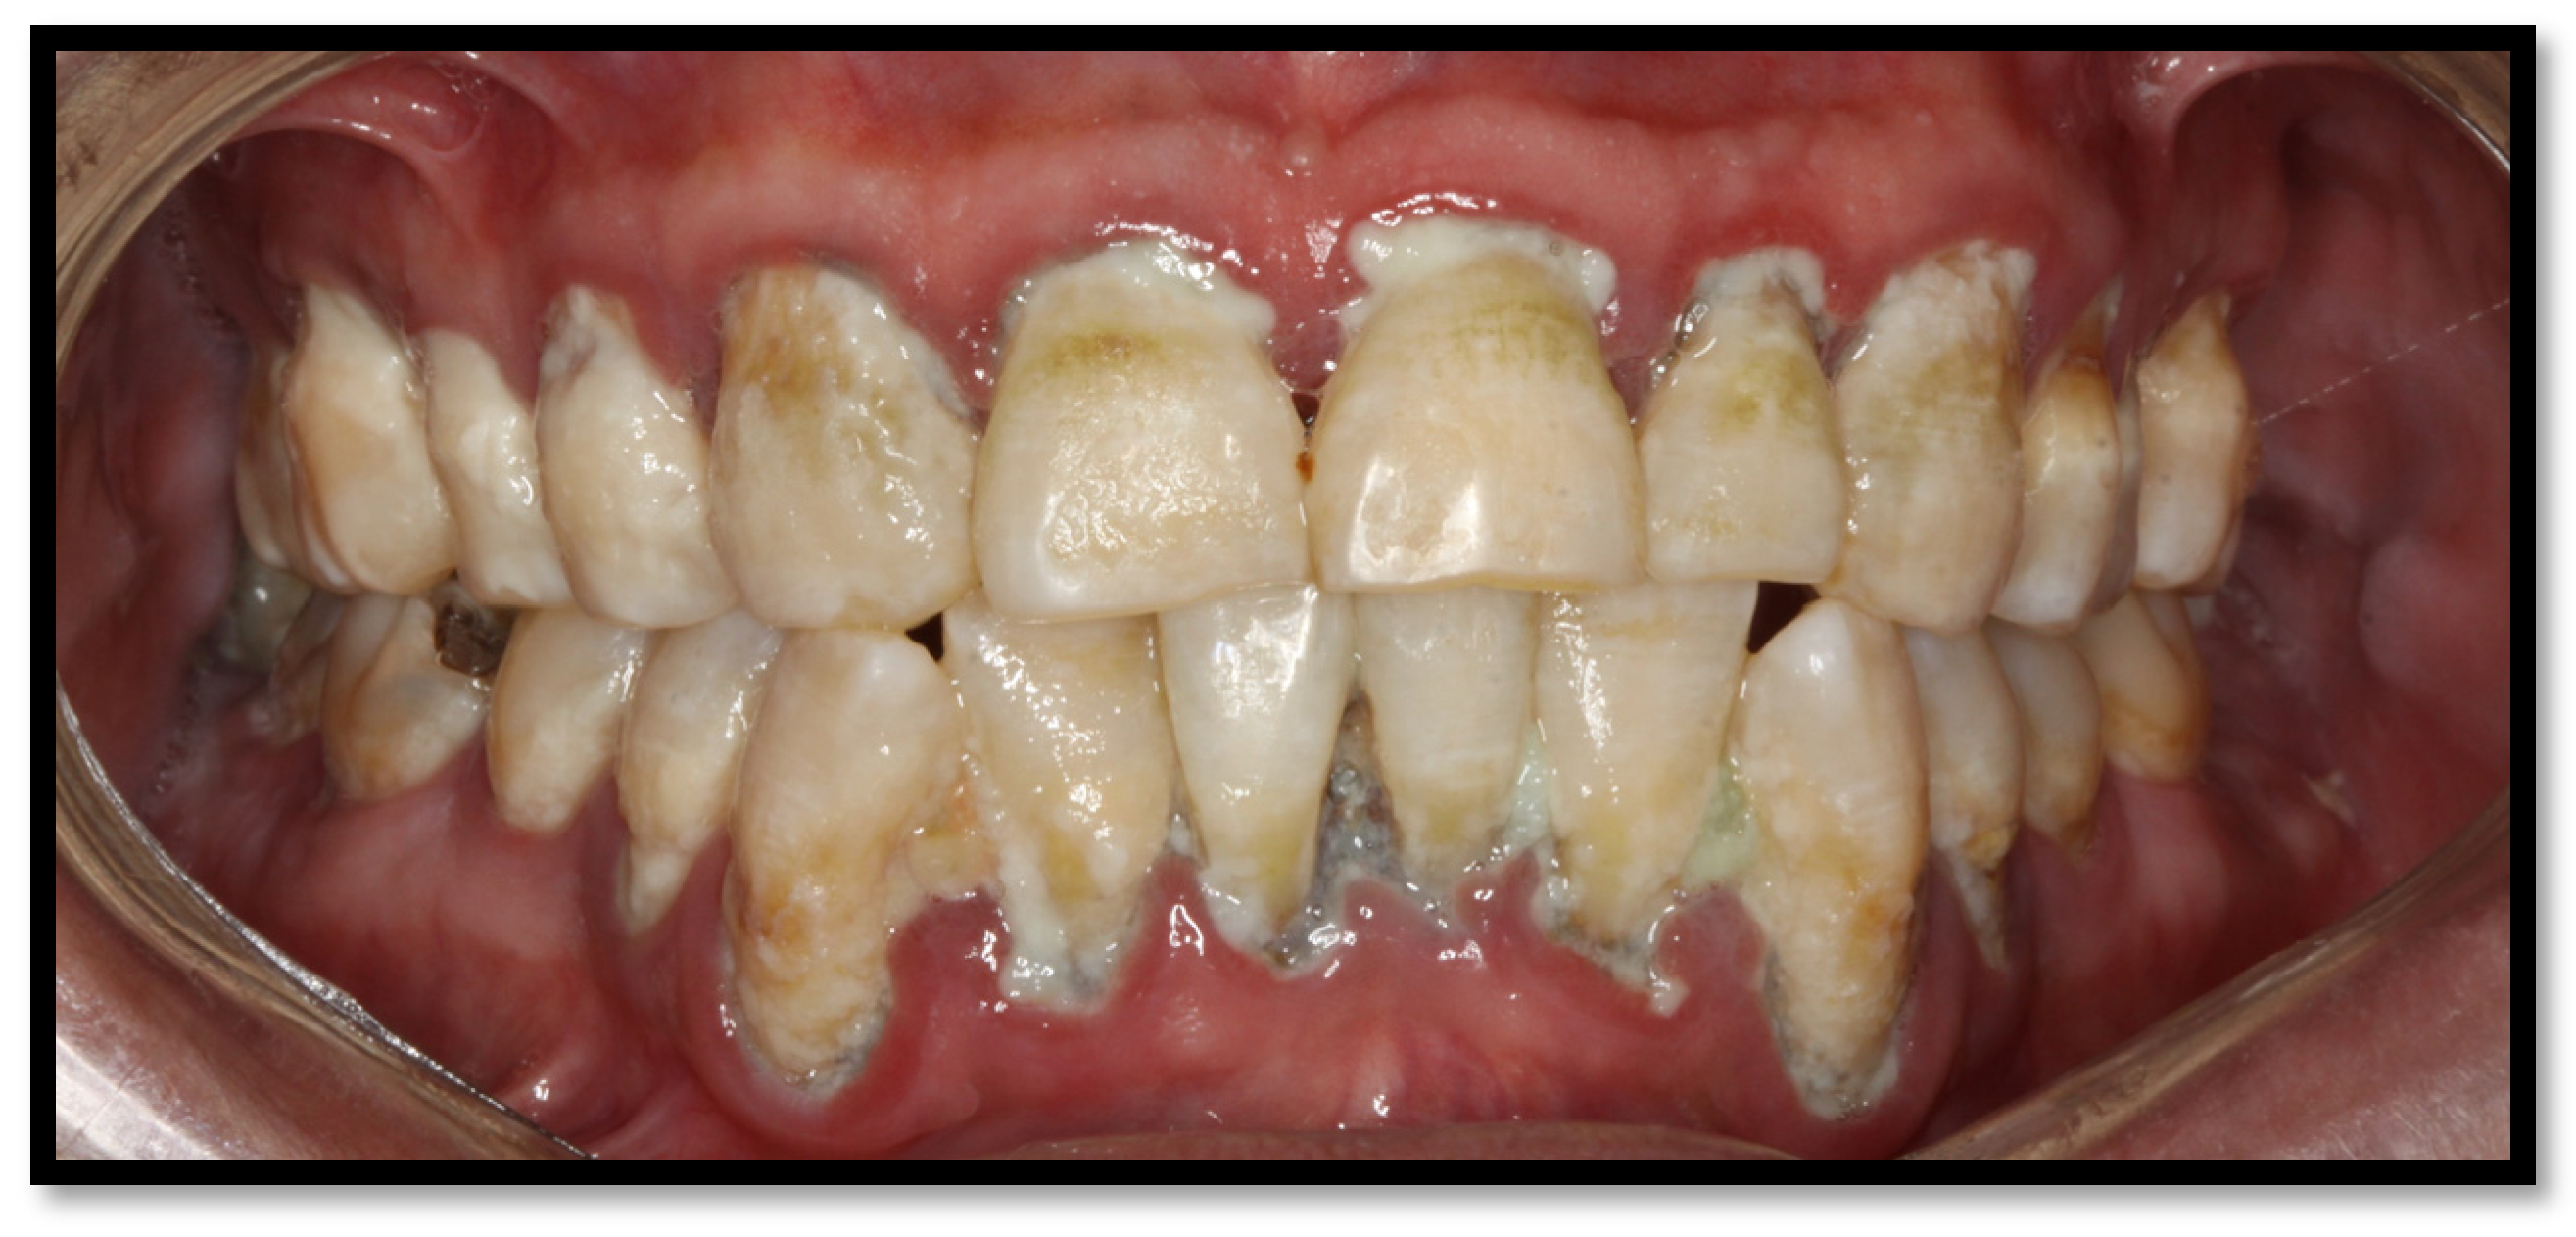

Oral hyperpigmentation appears in up to 37% of patients who have a CD4+ T lymphocyte count of <100 cells/μL. The causes of this condition remain unknown, though it has been associated with ART, particularly zidovudine, a thymidine analog reverse transcriptase inhibitor. Other drugs, such as clofazimine and ketoconazole, have also been associated, among others [16,45]. Oral hyperpigmentation manifests as black or maroon papules, associated with intraleukocytic melanin or pigments within the basal cell membrane or lamina propria, with premature melanosomes. It can show up anywhere on oral mucosal membranes [16,46] (Figure 12a,b). According to reports, HIV-positive patients are more frequently related to illicit drug use compared to the general population (28% vs. 16%, respectively) [47]. Methamphetamine use has been linked to developing dental disease, which might be relevant. These patients can show up with precarious oral hygiene, xerostomia, hypochromic lip lesions, lateral sides of cheeks and palate, accompanied by rampant caries (so-called oral “meth sores”), aside from grinding-related excessive dental wasting (Figure 13) [47].

Figure 13.

Hyperpigmentation in the lip mucosa, with severe dental destruction “methamphetamine mouth”.